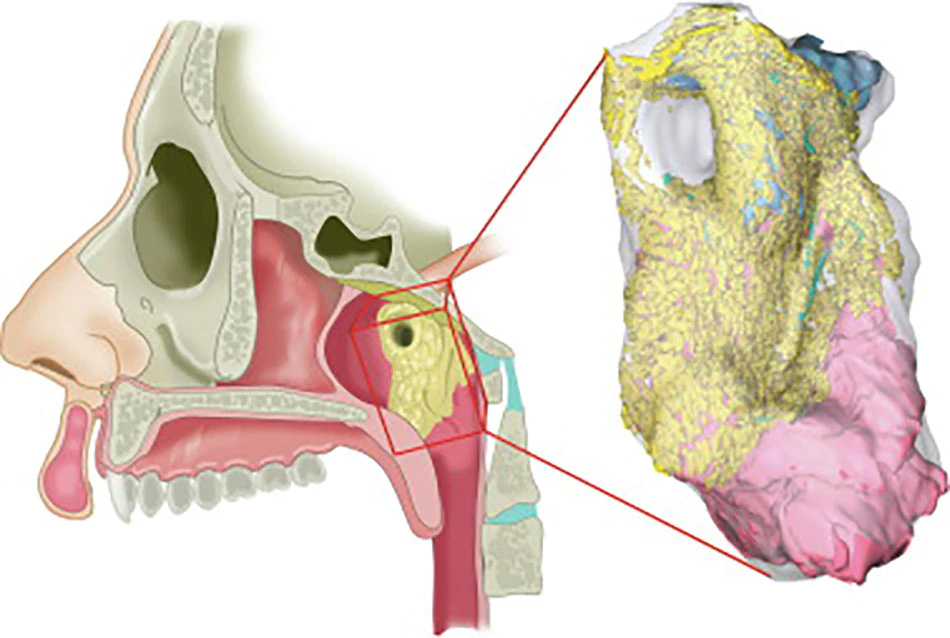

नीदरलैंड के एम्सटर्डम के कैंसर इंस्टीट्यूट के वैज्ञानिक प्रोस्टेट कैंसर की जांच के लिए तैयार किए गए PSMA PET-CT नाम के स्कैन का परीक्षण कर रहे थे। इस दौरान डॉक्टर्स एक रेडियोएक्टिव ट्रेसर को मरीज के शरीर में इंजेक्ट करते हैं। रेडियोएक्टिव ट्रेसर की वजह से ही नए अंग का पता चला। स्टडी में दावा किया गया है कि ये ग्लैंड 1.5 इंच के हैं और ये टोरस ट्यूबेरियस (Torus Tubarius) नाम के कार्टिलेज के एक हिस्से के ऊपर हैं। रिसर्चर्स का कहना है कि शायद इनका काम नाक और मुंह के पीछे गले के ऊपरी हिस्से को ल्यूब्रिकेट करना होगा।

रेडियोथेरपी ऐंड ऑन्कॉलजी जर्नल में छपी स्टडी में रिसर्चर्स ने पुष्टि की है कि करीब 100 मरीजों पर स्टडी में ये ग्लैंड पाए गए हैं। माना जा रहा है कि इस खोज से कैंसर के इलाज में मदद मिल सकती है। अभी तक माना जाता था कि नाक के पीछे के इस हिस्से (Nasopharynx) में कुछ नहीं होता है। वहीं, तीन सलाइवरी ग्लैंड भी जीभ के नीचे, जबड़े के नीचे और जबड़े के पीछे होते हैं, यही माना जाता था।